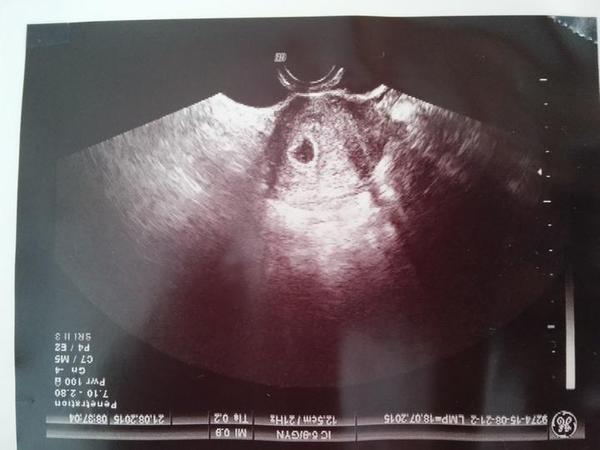

@martuska00 no nechuti mi jest musim sa premahat dost...aj to com som lubila sa pozriem a je mi na grc 😖 ja budem rada ked pojdem na embryjko v pondelok to budem 6tt+6 lebo v piatok este nebolo nic vidiet len plodovy a zltkovy vak sice aj ked neviem mne sa zda ze vidim tam aj embryjko ...

@martuska00 ja si myslim ze to biele je embryjko...to cierne je vak,to mensie je zltkovy vacok ale to biele ???????, 😕 😕 😕 😕

@isabella22 vobec sa nad tym nezamyslaj, tento prvy UTZ sluzi na potvrdenie toho ci sa baby usadilo v maternici. Mas super fotku a embryjko tam krasne vidno.

@ada274 vsak mi aj povedala ze to je normlany nalez na 20.den po ket...o 10 dni by malo byt vidno pekne embryjko aj srdiecko....tak sa tesim no zaroven aj obavam v pondelok...